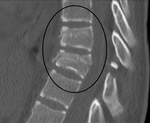

Chance fracture George Quentin Chance horizontal fracture of vertebral body hyperflexion of spine, seen in car accidents when lap belts were used Chance fracture Archived 2018-07-06 at the Wayback Machine at Wheeless' Textbook of Orthopaedics online PchancefracCT.png